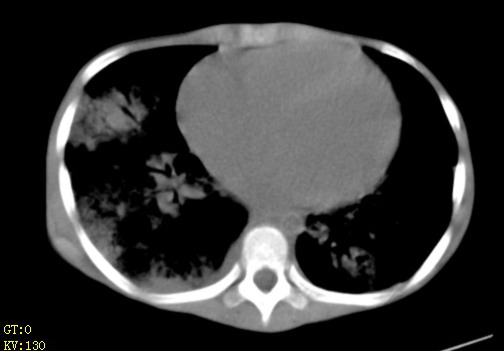

女,12岁,气促、咳嗽2天,3个月前查胸片示:两肺感染,急诊入院查ct,血常规等未检查。

先心(室缺?)、左室大,心功能不全;肺部感染

心衰 肺水肿

左肺上叶改变考虑继发性肺结核,余双肺重症肺炎不排除h1n1。双侧胸腔少量积液。

两肺感染,双侧少量胸腔积液;肺淤血及心脏改变,考虑心功能不全改变。学习了,望能反馈随访结果。

1、左心房、左心室增大,考虑左心衰, 2、肺水肿合并感染 3、双侧胸腔积液

双肺中下野不规则片絮状阴影,中外带明显,双侧胸腔少量积液,心影增大,心腔密度减低,隆突下及左侧气管旁见钙化淋巴结影,考虑双肺感染、心衰;建议结合临床除外h1n1并急性心衰,先心不能排除。

两肺多发片絮状模糊影,以下肺外带居多,内见支气管气像,纵膈窗未减影,两侧胸腔积液,心影增大,结合心超,支持重症肺炎,非常时期,甲型h1n1流感不排除。